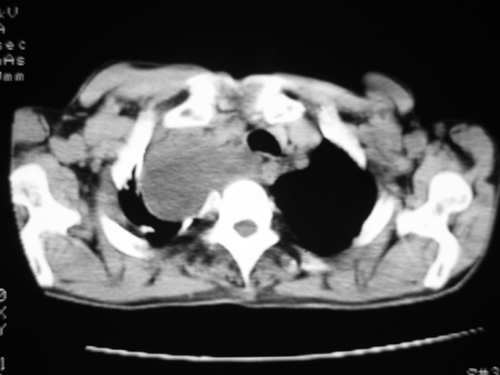

以下是引用yangyudong333在2008-4-29 5:46:00的发言:[br]1左上叶结节呈分叶状,边缘毛刺,考虑肺癌并纵隔淋巴结转移可能性大,结核待排,[br] [br]2右侧多发包裹性胸腔积液

以下是引用zsl6918在2008-4-29 9:15:00的发言:[br]右侧包裹性积液穿刺术后改变,肺内多发结节不除外转移可能。建议查胸水,问病史。